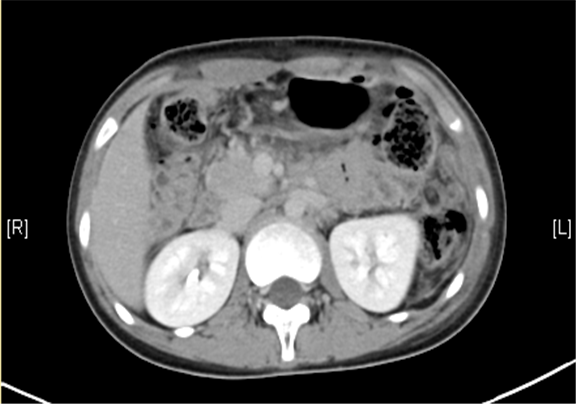

术后CT检查:

动脉期

静脉期

平衡期